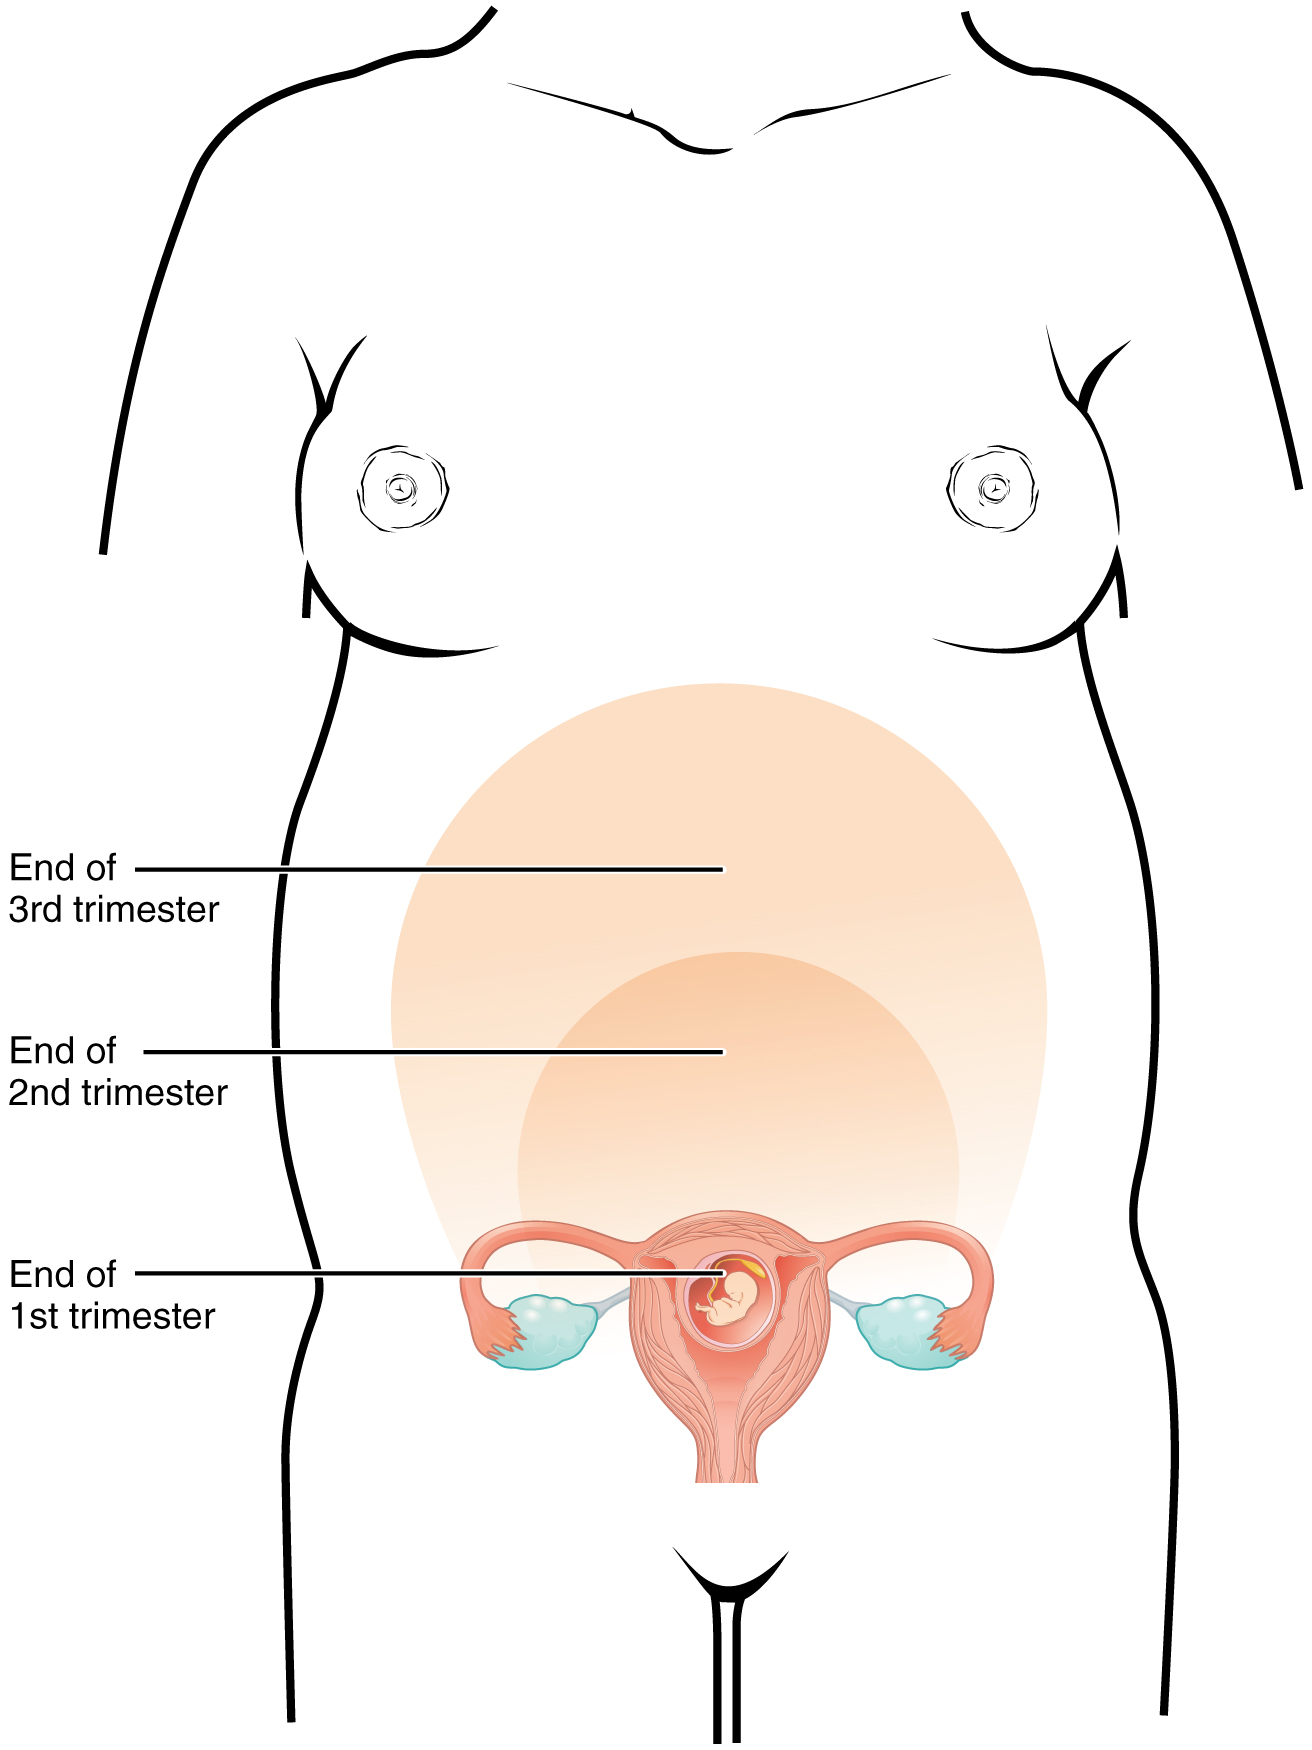

Chapter 10 – Conception, Pregnancy, and Birth – Introduction,

Chapter 10 – Conception, Pregnancy, and Birth – Introduction,![Pelvis with Pregnancy Model, 2 Parts [SKU: MG30131] – Nasco Pelvis with Pregnancy Model, 2 Parts [SKU: MG30131] – Nasco](https://shop.nascohealthcare.com/cdn/shop/files/SR20_535x.jpg) Pelvis with Pregnancy Model, 2 Parts [SKU: MG30131] – Nasco,

Pelvis with Pregnancy Model, 2 Parts [SKU: MG30131] – Nasco, Chapter 10 – Conception, Pregnancy, and Birth – Introduction,

Chapter 10 – Conception, Pregnancy, and Birth – Introduction,![Pelvis with Pregnancy Model, 2 Parts [SKU: MG30131] – Nasco Pelvis with Pregnancy Model, 2 Parts [SKU: MG30131] – Nasco](https://shop.nascohealthcare.com/cdn/shop/files/SR20-04_400x@2x.jpg) Pelvis with Pregnancy Model, 2 Parts [SKU: MG30131] – Nasco,

Pelvis with Pregnancy Model, 2 Parts [SKU: MG30131] – Nasco, Chapter 10 – Conception, Pregnancy, and Birth – Introduction

Chapter 10 – Conception, Pregnancy, and Birth – IntroductionCreating Beautiful Boxes With Inlay Techniques (shin